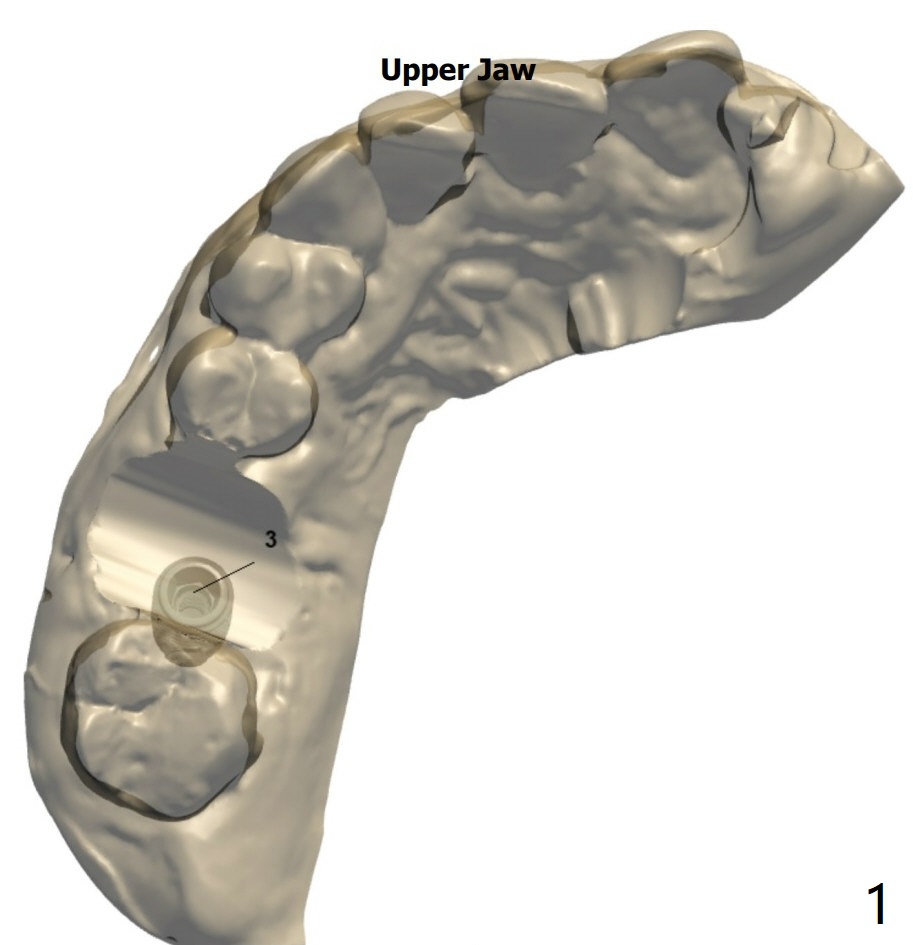

Implant Placement Level and Angulation to Sinus Floor

Return to No Deviation Torque 劈开术